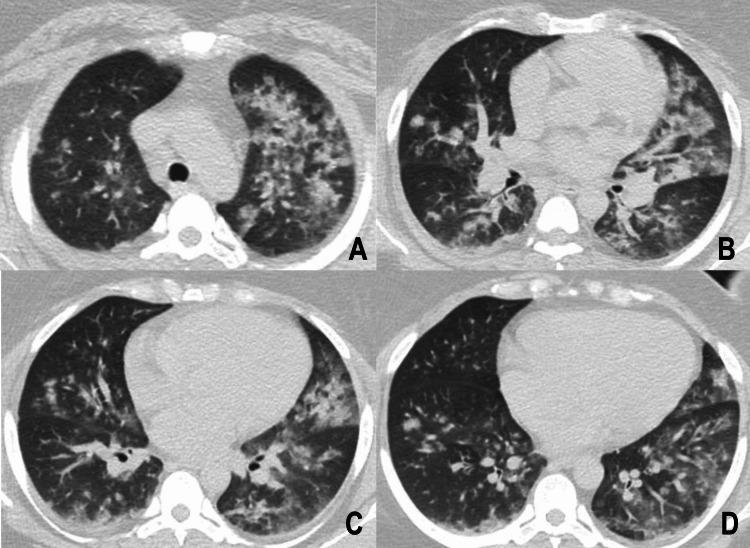

Cocaine, the second most used illicit drug, is associated with cardiovascular, pulmonary, and other complications. Lung involvement associated with cocaine use, also known as "crack lung syndrome" (CLS), can elicit new-onset and exacerbate chronic pulmonary conditions. A 28-year-old female with a history of chronic controlled asthma arrived at the Emergency Department (ED), referring to cocaine inhalation, followed by symptoms compatible with an asthmatic crisis, requiring immediate steroid and bronchodilator therapy. Radiological studies and bronchoscopy confirmed CLS diagnosis. Despite treatment with oxygen, bronchodilators, and steroids, the asthmatic crises persisted. However, after 48 hours, we observed a complete regression of the lung infiltrates. This case highlights the importance of clinical suspicion, bronchoscopy findings, and the potential co-occurrence of CLS with asthma exacerbations. While computed tomography (CT) scans can be helpful, they should not be the only tool to diagnose CLS. The successful management of CLS involves the use of bronchodilators, steroids, and oxygen therapy and abstaining from cocaine use. Researchers should conduct further studies to diagnose and treat CLS in conjunction with acute asthma symptoms to assist this patient population better.

可卡因是第二大常用非法药物,与心血管、肺部及其他并发症相关。与使用可卡因相关的肺部受累,也称为“快克肺综合征”(CLS),可引发新发疾病并加重慢性肺部疾病。一名有慢性可控性哮喘病史的28岁女性来到急诊科(ED),称吸入了可卡因,随后出现与哮喘发作相符的症状,需要立即进行类固醇和支气管扩张剂治疗。影像学检查和支气管镜检查确诊为CLS。尽管给予了吸氧、支气管扩张剂和类固醇治疗,但哮喘发作仍持续。然而,48小时后,我们观察到肺部浸润完全消退。该病例凸显了临床怀疑、支气管镜检查结果以及CLS与哮喘发作可能同时出现的重要性。虽然计算机断层扫描(CT)有助于诊断,但它不应是诊断CLS的唯一工具。CLS的成功治疗包括使用支气管扩张剂、类固醇和氧疗,并戒除可卡因使用。研究人员应开展进一步研究,以便结合急性哮喘症状诊断和治疗CLS,从而更好地帮助这一患者群体。